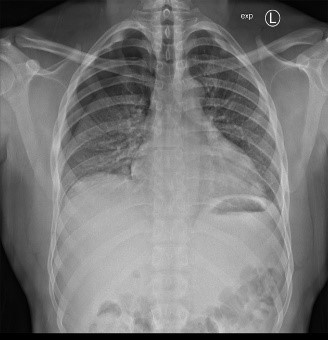

Bildergalerie (5 Bilder)